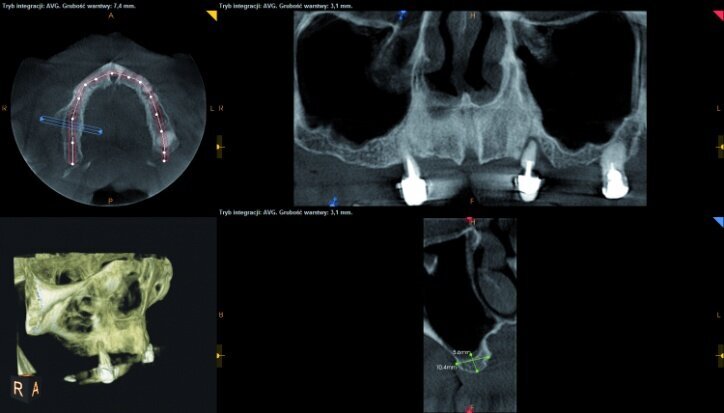

During the process of treatment planning, a few proposals for prosthetic solutions were presented, including permanent and temporary restorations, based on existing teeth as well as implants of various combinations. After analysing CBCT scans (Figs. 3–6) it could be concluded that implantological treatment may be performed at the front maxilla without any additional procedures, however, due to significant atrophy in the lateral part and a low-lying fundus of the left and right maxillary sinus, it appeared necessary to perform augmentation procedures (sinus lift), in order to make implantation possible.